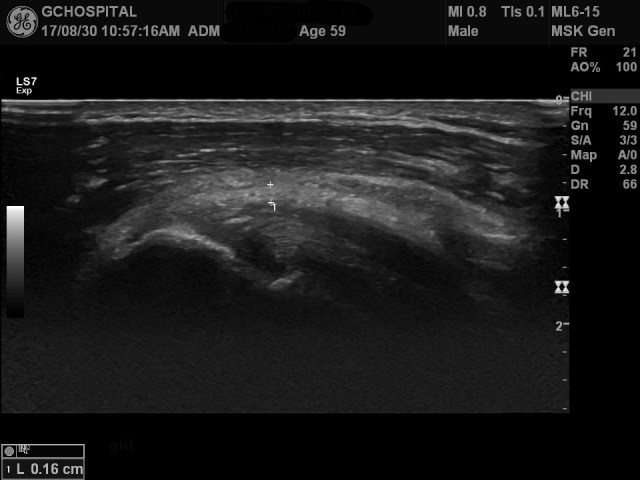

59세 남자환자로 왼쪽 어깨의 통증과 운동범위 제한을 주소로 내원한 환자로, 임상에서는 회전근개파열의 가능성을 의심해서 초음파를 의뢰하여 시행한 영상입니다.

초음파영상에서 회전근개파열이나 퇴행성 변화는 보이지 않았지만, 위 영상에서처럼 joint capule(두께를 측정한 곳의 바깥쪽)과 coracohumeral ligament(1.6mm로 측정된 부위)가 모두 상당히 두꺼워져 있었으며, 견관절의 외회전(external rotation)시 통증을 호소하였습니다.

보통 adhesive capsulitis의 경우는 coracohumeral ligament의 두께가 평균 1.5mm 이상인 반면, 정상 내지 무증상군에서는 0.9mm정도라고 하며, 이렇게 coracohumeral ligament가 두꺼운 경우는 adhesive capsulitis의 가능성을 시사합니다.